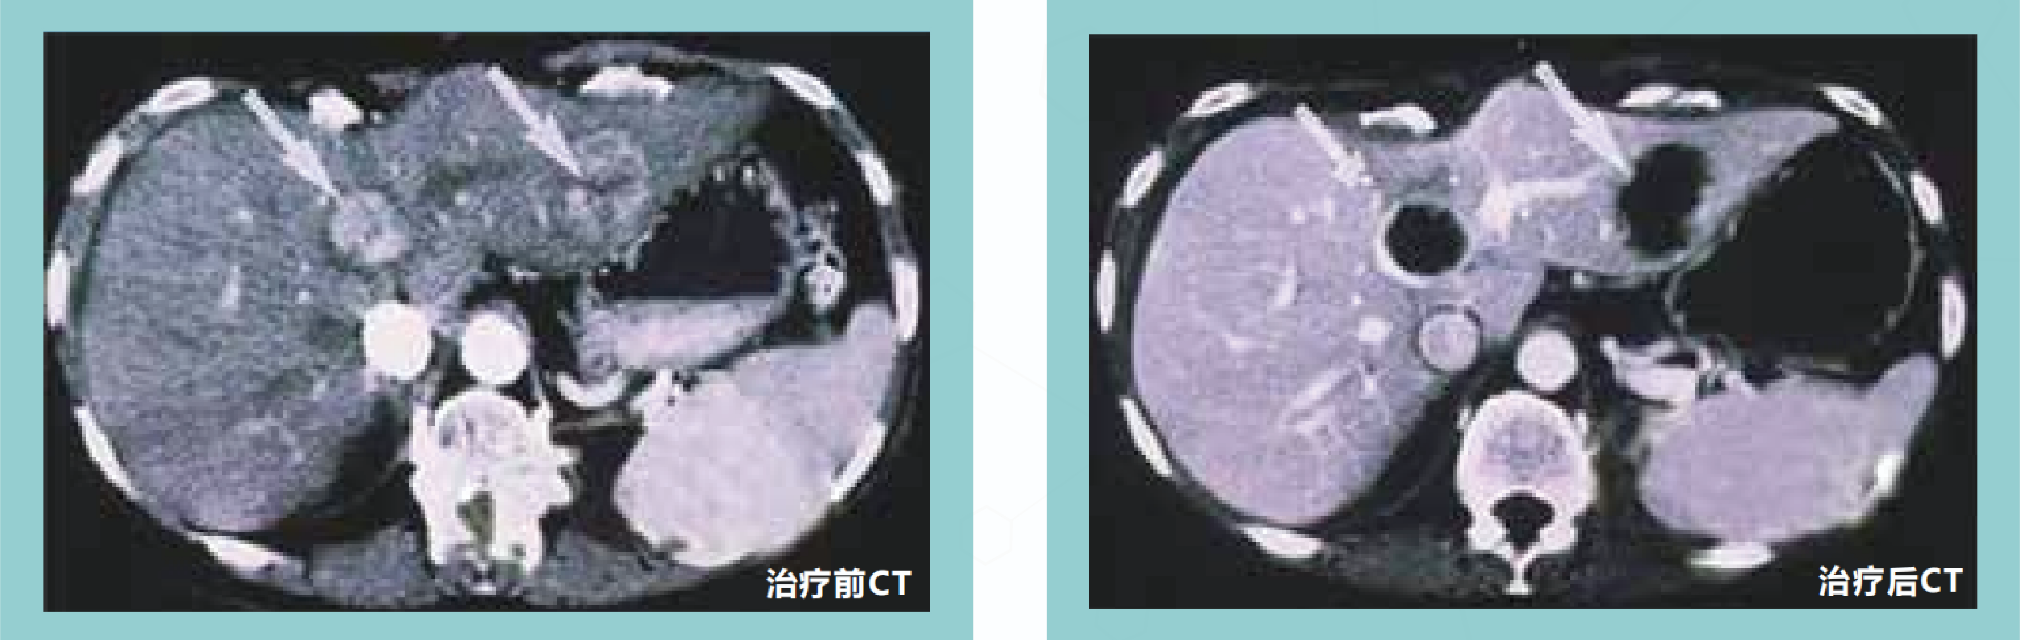

在超声或CT的引导下经皮穿刺肿瘤中心后,注射化学消融剂,直接作用于肿瘤组织蛋白,使癌细胞脱水固定,蛋白质凝固变性,破坏肿瘤细胞,凝固坏死组织可逐渐被吸收或瘢痕化,而周围组织无显著损伤。

经皮化学消融治疗对直径小于2厘米的肝癌有效率为90%~100%,对直径3厘米左右的肝癌有效率为70%。

经皮化学消融